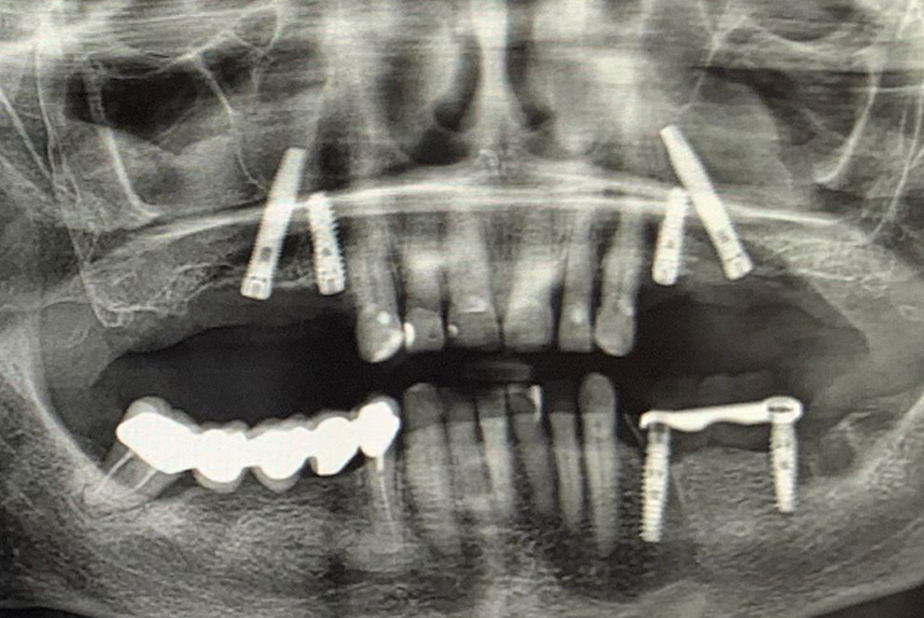

A seguito di un'accurata valutazione clinica e radiografica preparatoria (Fig. 1) è stato pianificato l'inserimento di impianti IS+ (BTK) nelle regioni anteriori e di impianti BT-Rhyno (BTK) nei settori posteriori mediante tecnica transinusale.

Fig. 1 - Valutazione clinica e radiografica preoperatoria